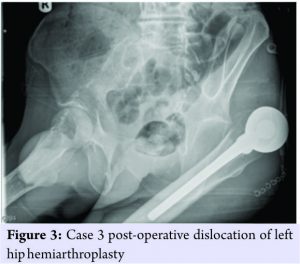

Case 3

An 83-year-old female suffered a displaced right hip intracapsular neck of femur fracture. She underwent right hip hemiarthroplasty with the following components: Corail uncemented femoral stem size 14 with collar and self-centering bipolar head size 22.225 mm/46 mm (DePuy Ltd., Ringsakiddy, Cork, Ireland). Her medical background was significant for severe Parkinson’s disease and dementia. Preadmission patient was a non-ambulatory and need full hoist transfer. Post-operative course was complicated by pneumonia. Day 19 postsurgery, following hoisting from bed to wheelchair the right lower limb was noted to be shorted and rotated and patient was subjectively in pain. X-ray confirmed dislocation (Fig. 3). The patient underwent Girdlestone procedure given her preadmission status and complicated post-operative course. The patient was transferred to long-term care for palliative care after deterioration in her condition and died 35 days after initial surgery.